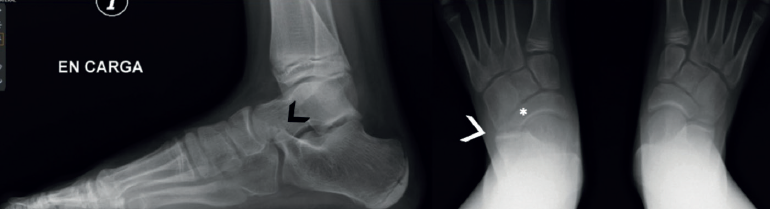

El pico del astrágalo (talar beak) se produce secundariamente por la rigidez del retropié(45). La articulación de Chopart aumenta su movilidad a dorsal, el escafoides sube por encima de la cabeza del astrágalo creando con la tracción capsular un pico (es más común en las TC que en las CN) (Figura 7).

El signo de la C o C-sign es el signo directo más fácil de identificar en la vista lateral. Analizando la faceta medial de la articulación subastragalina en las coaliciones TC, que son las más frecuentes (Figuras 7 y 8). Si es distrófico o la línea articular es irregular, sugiere osteoartritis. Los pacientes suelen ser jóvenes al diagnóstico. Posteriormente, en caso de sinostosis con continuidad entre el calcáneo y el astrágalo, un bloque óseo une la voluminosa faceta medial distrófica al sustentaculum tali. Tiene la forma de un arco convexo posteriormente: de ahí el “signo de la C”(45). En pies planos puede ser positivo sin coalición(46) (sensibilidad del 88% y especificidad del 87%)(22).

La ausencia de la faceta medial (subastragalina) precisa de una proyección exacta lateral centrada en el retropié(22). Si la articulación subastragalina posterior es visible y bien alineada, la anterior debiera ser igualmente visible; si no, es posible una coalición(22,47) (sensibilidad del 72-100% y especificidad del 42-94%) (Figura 8A).

Drunken waiter sign o signo del “camarero borracho” (Figura 5): si se aprecia en las radiografías axiales del calcáneo de Harris un ángulo superior a 20° entre la superficie del sustentaculum y la posterior, se sospechará una coalición, con una sensibilidad del 72% y una especificidad del 94% que se debe confirmar en cortes coronales de TAC.